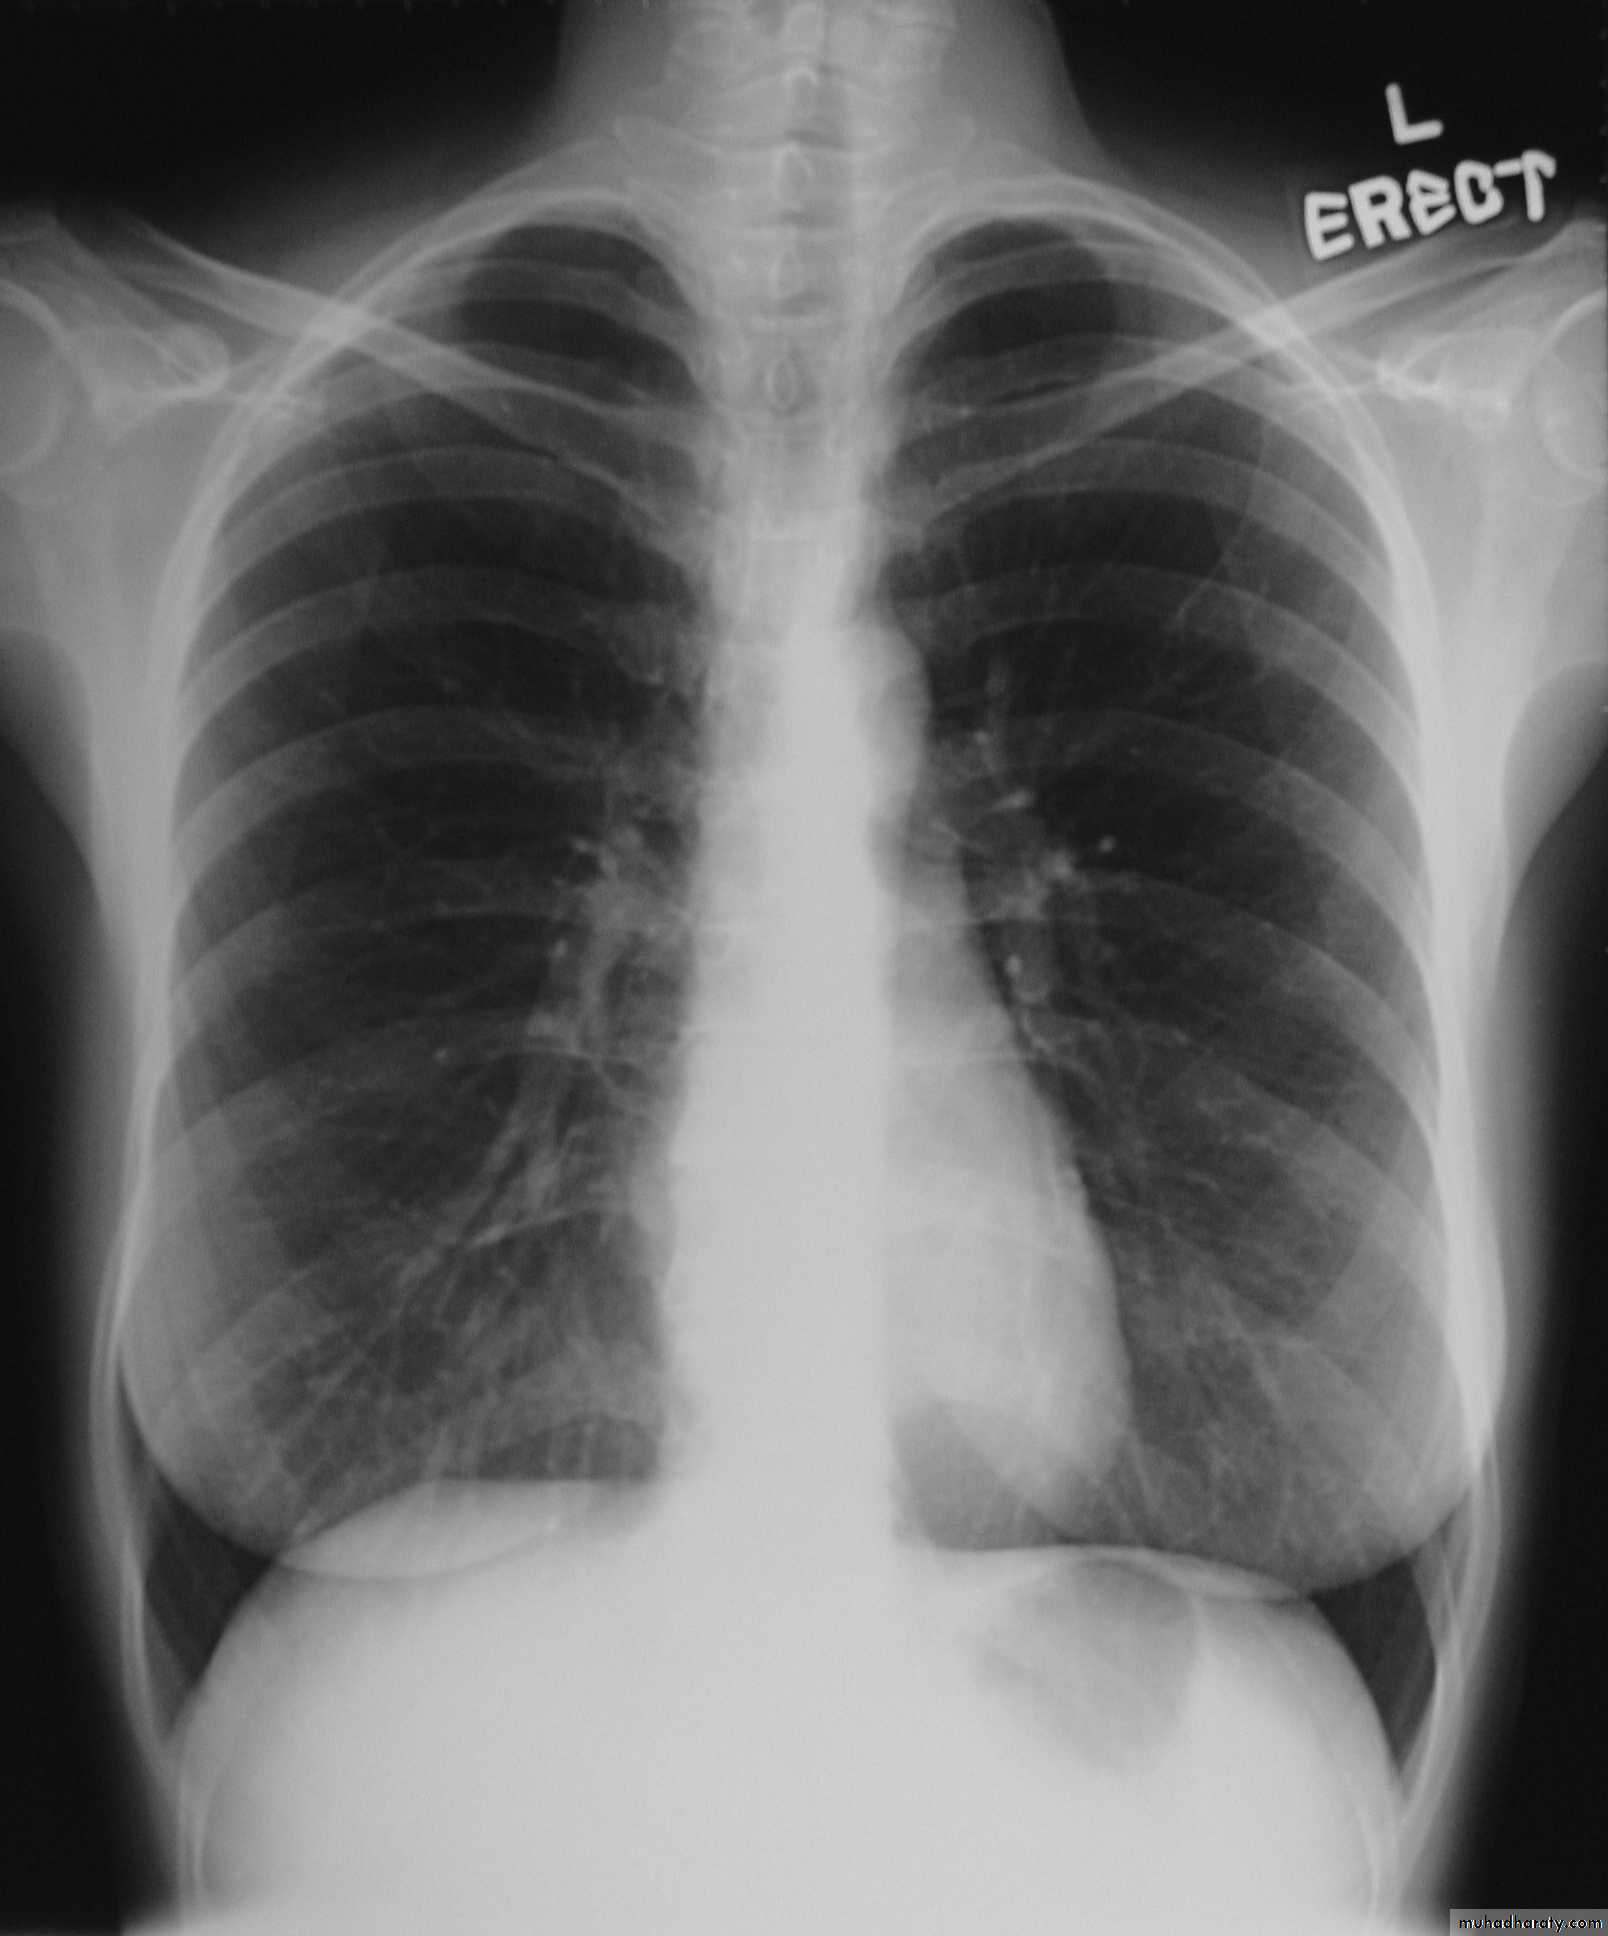

Chest X-ray: widening of the mediastinum, aspiration pneumonia.A barium swallow: tapered narrowing of the lower esophagus, esophageal body is dilated, aperistaltic and food-filled.

Barium swallow findings:

Tapered narrowing of the lower esophagus, esophageal body is dilated, aperistaltic and food-filled.Clinical features: